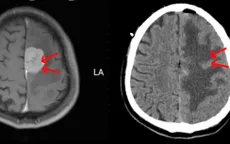

Đau đầu, yếu liệt nửa người vì khối u màng não lớn

VTV.vn - Nam bệnh nhân 67 tuổi, trú tại Thanh Hóa có biểu hiện đau đầu, yếu liệt nửa người, tình trạng này kéo dài hơn 1 năm nay và tăng dần lên.